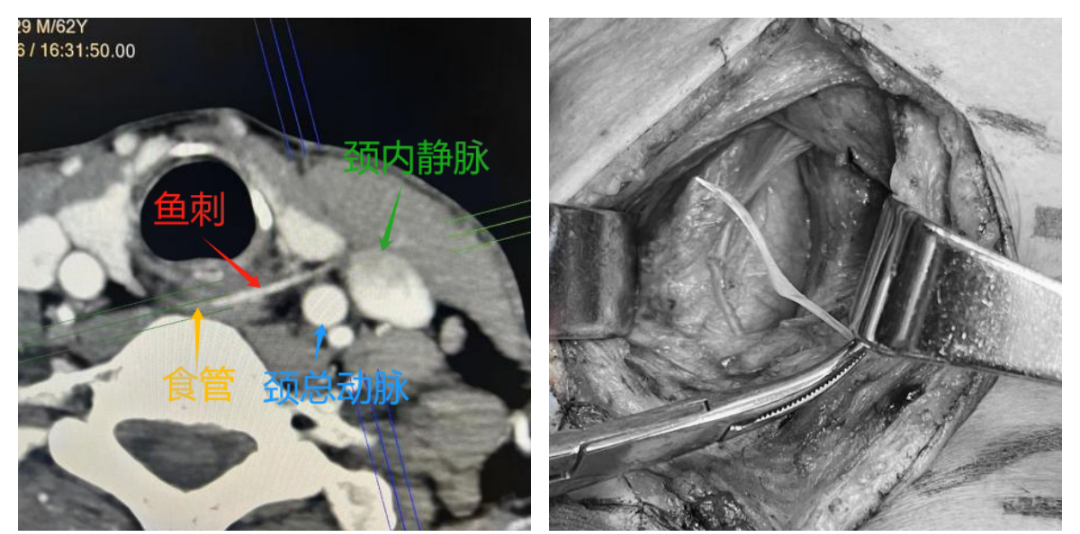

危急时刻,耳鼻咽喉科赵宁副教授迅速赶到。经过高效严谨的术前准备,耳鼻咽喉科、麻醉科、手术室团队紧密协作,颈深部异物探查术、颈侧切开食管异物取出术即刻开展。

全麻下,术者探查发现鱼刺尖端紧紧抵住颈部大血管,与术前研判完全一致。团队沉着应对、精准把控,每一步操作均做到分毫无差,避免对血管及周围组织造成二次损伤。最终,术者凭借精湛的外科技术,将这根“致命鱼刺”完整钳夹取出,手术过程顺利,未出现任何术中并发症。术后患者安返病房,生命体征平稳。